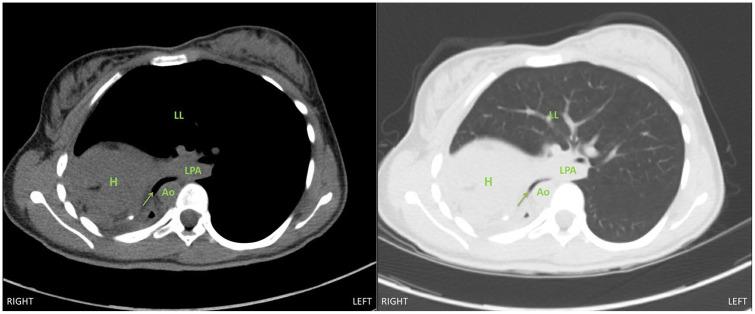

Postpneumonectomy syndrome is a rare complication in patients who have previously had a pneumonectomy. Over time, the mediastinum may rotate toward the vacant pleural space, which can cause extrinsic airway and esophageal compression. As such, these patients typically present with progressive dyspnea and dysphagia. There is a paucity of reports in the anesthesiology literature regarding the intraoperative anesthetic approach to such rare patients. We present a case of an 18-year-old female found to have postpneumonectomy syndrome requiring thoracotomy with insertion of tissue expanders. Our case report illustrates the complexities involved in the care of these patients with regards to airway management, ventilation concerns, and potential for hemodynamic compromise. This case report underscores the importance of extensive multidisciplinary planning.

肺切除术后综合征是既往行肺切除术患者的一种罕见并发症。随着时间的推移,纵隔可能向空的胸膜腔旋转,这可能导致气道和食管受压。因此,这些患者通常表现为进行性呼吸困难和吞咽困难。麻醉学文献中关于此类罕见患者的术中麻醉方法的报道很少。我们报告了一例 18 岁女性患者,发现患有肺切除术后综合征,需要行开胸手术并插入组织扩张器。我们的病例报告说明了在气道管理、通气问题以及潜在的血液动力学受损方面,对这些患者进行护理所涉及的复杂性。本病例报告强调了广泛的多学科规划的重要性。